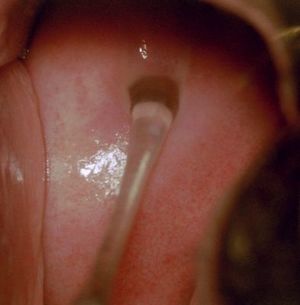

Human vagina with view of the Skenes Glands | |